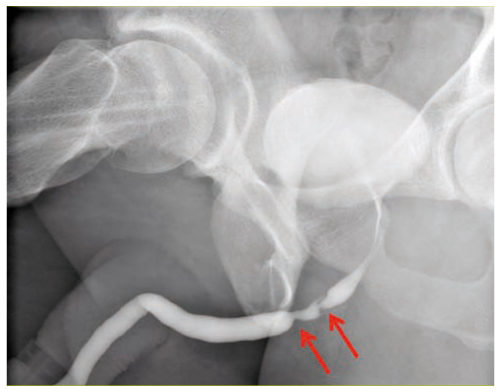

La sonde double J est un tube souple et fin (environ 3 mm de diamètre) dont les extrémités forment chacune une boucle (d’où le terme double J) ce qui permet à la sonde de rester en place entre le rein et la vessie.

Les sondes double J sont introduites dans l’uretère par les voies naturelles.

Une sonde double J est mise en place pour prévenir ou contourner un obstacle au niveau de l’uretère.

Le traitement des calculs du rein ou de l’uretère est l’indication la plus fréquente de pose de cette sonde JJ.